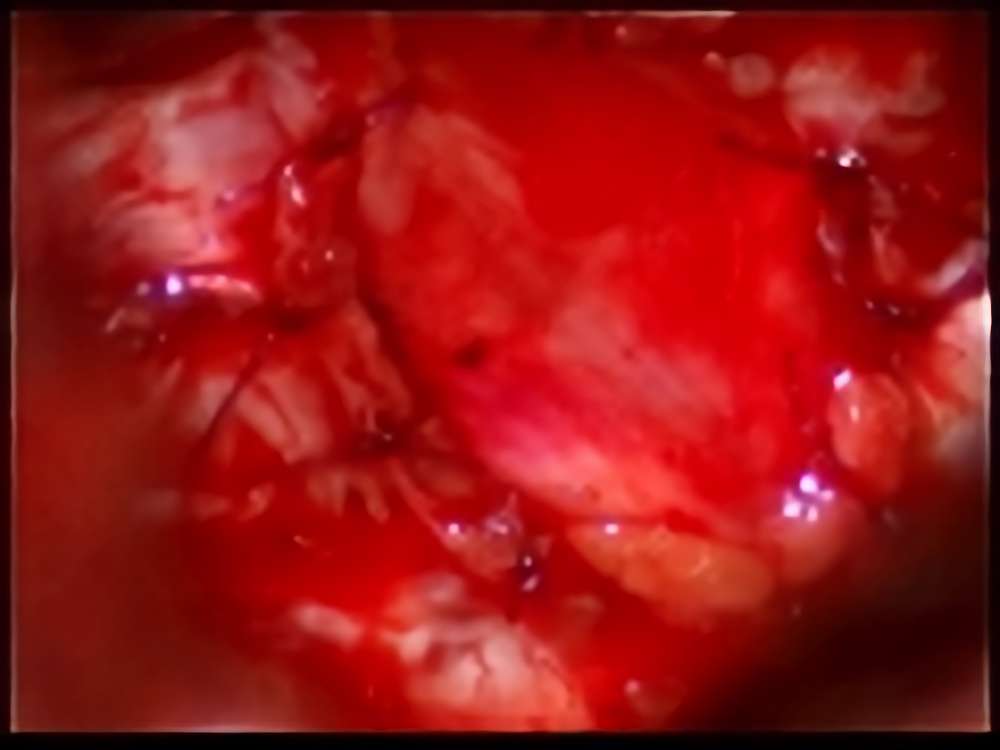

術中写真

摘出 前

摘出 中

摘出 後